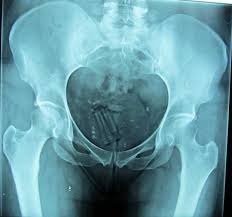

El interno debió quedar internado en observaciones bajo el diagnostico de “cuerpo extraño en zona rectal”.

Según las fuentes, el detenido había ocultado en su recto un paquete que contendría sustancias prohibidas.